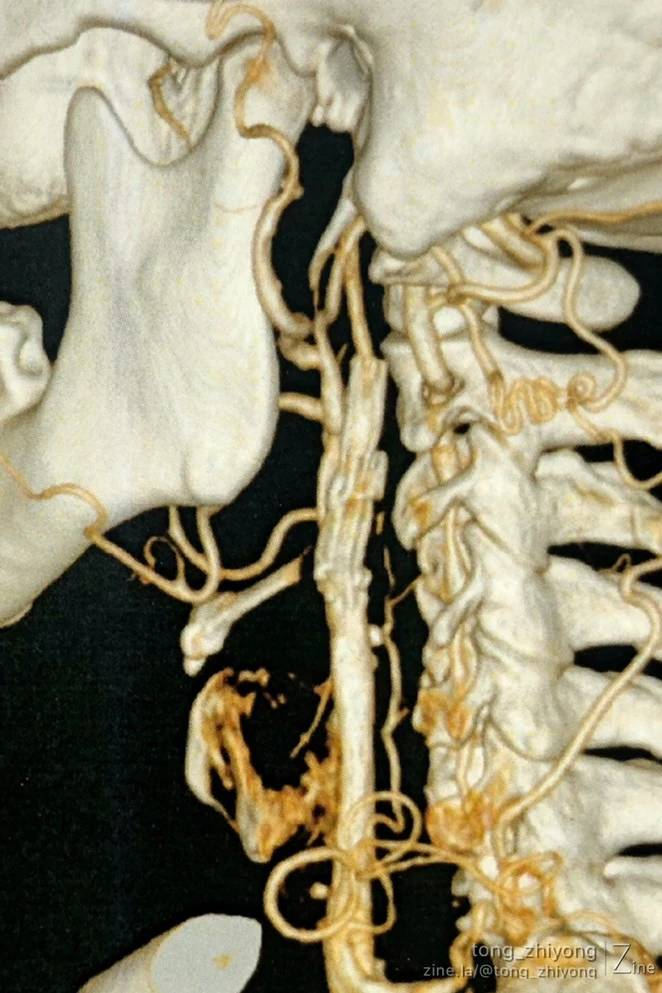

显露到支架远心端颈内动脉,确认:颈内动脉内释放的6mm支架的直径“大于”远心端颈内动脉的直径。

将斑块和支架一起切除,一并切除支架远心端部分颈内动脉内膜。

术后一周CTA显示:颈部操作最上端到达C1锥体水平。钛结扎夹在CTA上像“香米粒”一样。

完全开通左侧颈动脉